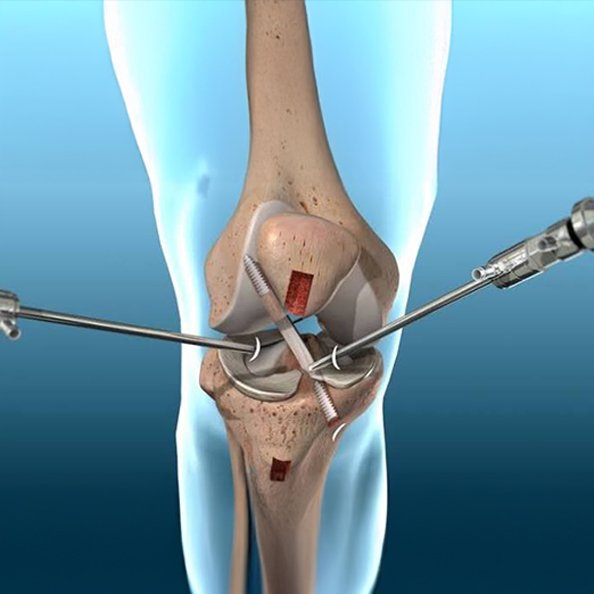

Knee Arthroscopy Surgery

Minimally invasive knee arthroscopy surgery for injuries and Ligament Tear ( ACL, PCL, MCL, LCL), Meniscus Tear, Cartilage Loss ensuring precision treatment, faster recovery, and improved joint function.